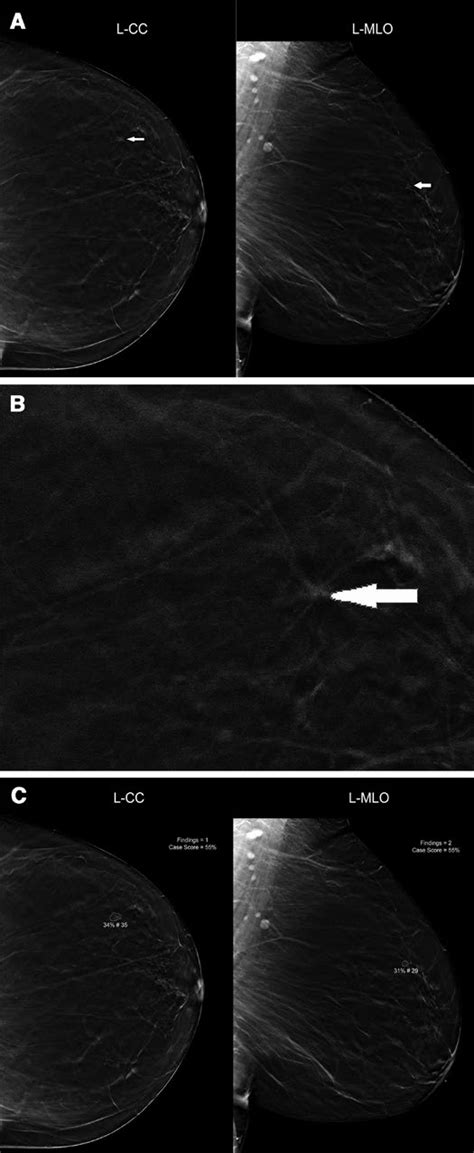

6. Mammogram: A Lifesaving Tool for Women

Mammogram breast cancer screening

Mammography is an X-ray imaging technique used to detect breast cancer early, when it is most treatable. Regular mammograms are recommended for women over the age of 50. Talk to your doctor about the recommended screening interval based on your personal risk factors.